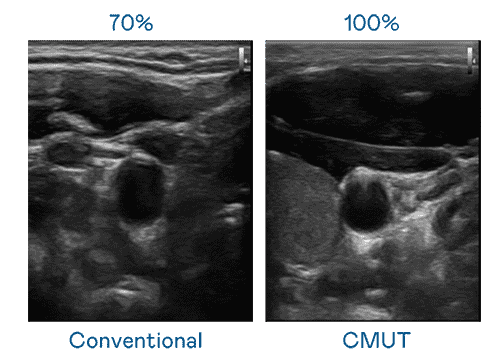

CMUT 技术是一种用电容式微机电元件来产生超音波讯号的技术。。。与传统 PZT 压电式技术相比,,,CMUT 频宽增加 30%,,,更宽频的超音波讯号让影像解析度大幅提升,,,,是实现高影像品质医疗超音波扫描、、、促进精准医疗发展的关键技术。。。。

大频宽带来超清晰影像

超音波影像的解析度高低,,首先取决于探头能发出的讯号频宽。。巨星国际 CMUT 可提供高清晰的超音波讯号,,,提供高频宽、、、、高灵敏度、、影像纹理细节更高的超音波影像,,,协助医护人员缩短影像判读时间及利用精准的医疗影像进行诊断。。